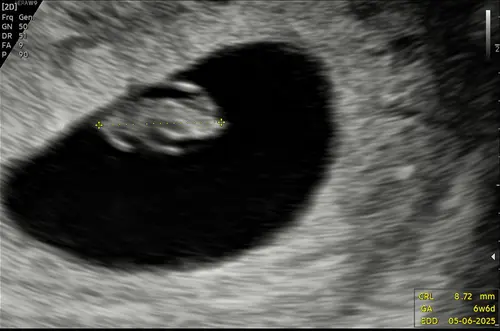

De gynaecoloog gaat altijd eerst een inwendige echo maken om te controleren of er echt geen hartactiviteit zichtbaar is voordat er medicatie wordt voorgeschreven. Hier zijn ze heel nauwkeurig in. Bij mij werd het zelfs nog door een tweede gynaecoloog gecontroleerd. Heel veel sterkte gewenst en ik hoop met je mee op een wonder.

Ik heb in december een missed abortion gehad. Doorverwezen naar de gynaecoloog en die heeft uitwendig en inwendig een echo gemaakt. Hij is wel 20 min bezig geweest om zeker ervan te zijn dat er niks over het hoofd werd gezien voordat ik de medicatie zou krijgen.

Gewoon duidelijk de situatie aangegeven en vragen dat ze in en uitwendig gaan kijken!